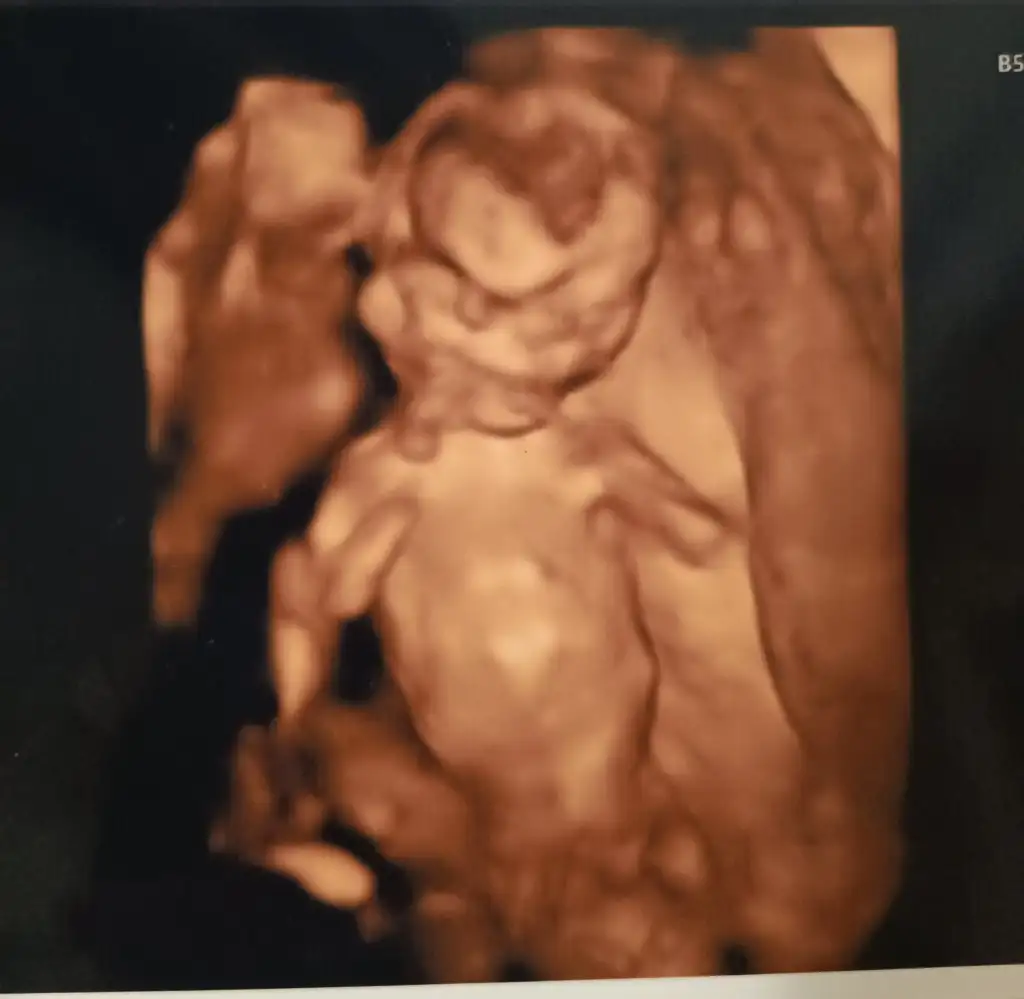

Erkek benceMerhabalar gençler14 haftalık bebişin cinsiyetini tahmin edebilen var mı acaba?